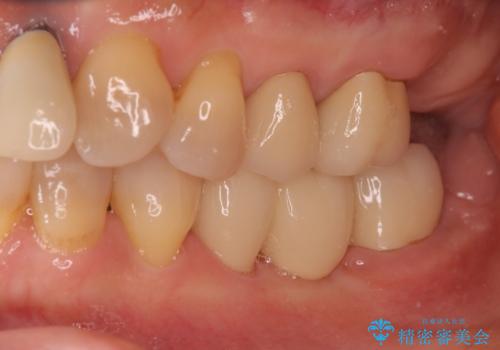

奥歯の部分矯正を行うことで、歯の傾きが良くなり、結果神経を取らずにブリッジを入れていくことができました。

通常矯正治療後は歯並びが戻らないように保定が必要ですが、ブリッジを入れているので歯並びは戻らないため保定が不要です。

部分矯正と補綴の相性は良いといえます。